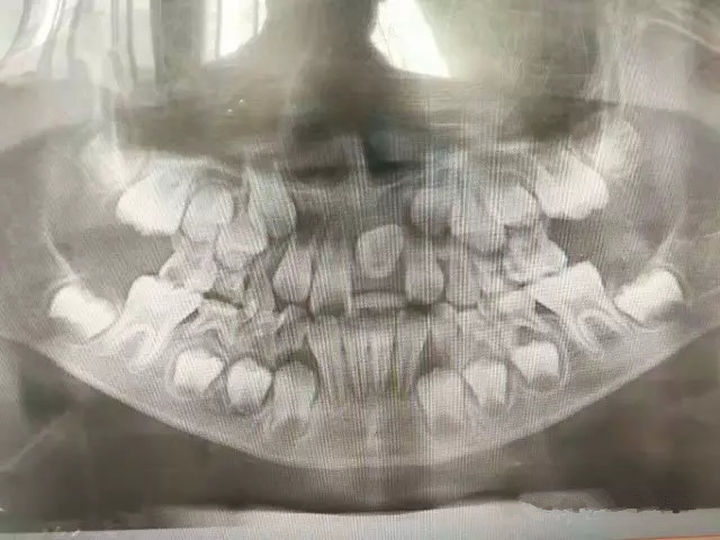

儿童出生萌牙后要定期进行口腔检查,早期发现问题早期预防,及早纠正孩子的不良习惯,乳牙龋坏的早期治疗,乳牙早失的缺隙保持,及时拔除滞留乳牙及多生牙。

若是替牙期若发现牙齿拥挤,便可采取顺序拔牙的方法来治疗。

大多数错合畸形在牙齿替换完成时进行常规矫治最为有利和高效。在恒牙初期进行矫治,女孩一般在11~13岁,男孩一般在12~15岁。 此时牙齿替换结束,恒牙列基本建立,颅颌面软硬组织发育尚有部分潜力,组织代谢功能好,牙齿移动效果最显著, 所以这个时期是正畸矫治的“黄金时期”。 严重的骨骼畸形在生长发育完成后再行手术治疗。